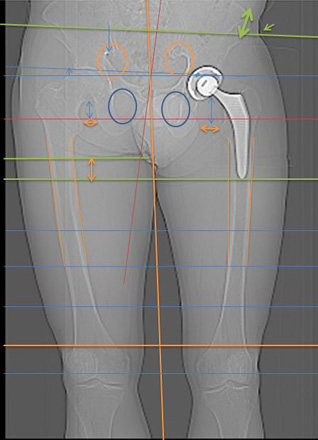

Abbildung Hüft / Teil Rücken / Teil Beine von hinten aufgenommen

1.5

1.6

Hüft mit Strichen Pfeilen Kreise sichtbar gemacht

Oberkörper weicht trotz Hüftgelenk Ersatz blau eingesetzte Striche aus.

Anhand der Gesässfalten wird auch der Beckentiefstand ersichtlich.

Über die Grüne Linie sieht man wie die rechte Seite geknickt wird.

Auf der linken Seite wird die Überdehnungsspannung sichtbar.

Würde die Ganz-Körper-Statik Vermessung eingesetzt, würde die Diagnose schnell und präzise die Ausweichhaltungen aufzeigen.

Würde die Ganz-Körper-Statik Vermessung bei den bildgebenden Verfahren eingesetzt, könnten Fehldiagnosen verhindert werden. Dies würde die Ursache der Skelett Ausweichhaltungen als Ursache der Muskelfehlspannungen aufzeigen.